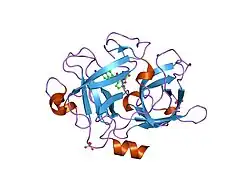

Urokinase is a 411-residue protein, consisting of three domains: the serine protease domain (consisting of residues 159–411), the kringle domain (consisting of residues 50-131), and the EGF-like domain (consisting of residues 1-49). The kringle domain and the serine protease domain are connected by an interdomain linker or connecting peptide (consisting of residues 132–158). Urokinase is synthesized as a zymogen form (prourokinase or single-chain urokinase), and is activated by proteolytic cleavage between Lys158 and Ile159. The two resulting chains are kept together by a disulfide bond between Cys148 and Cys279.[9]